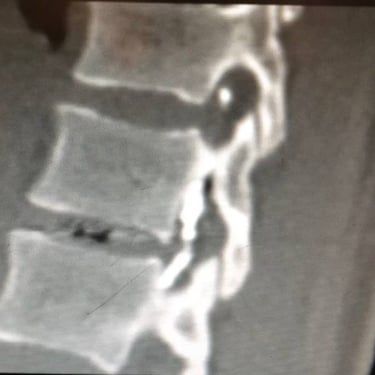

An intriguing case involved severe herniation and disc rupture between L4 and L5 vertebrae, causing intense pain. Opting out of surgery, the patient chose to try Discogel. Due to severe foraminal stenosis from the extruded disc, the Discogel injection was cautiously prolonged to one hour. Post-injection CT scan revealed effective penetration into fragmented disc components in the narrowed foraminal space.

The patient's pain gradually diminished after 4-5 weeks, and complete relief was achieved after several months.

The first image is six months post-injection, and the second image is three years post-injection."